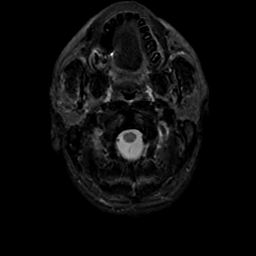

MR Study #22, December 1, 1991 -- Slice #1